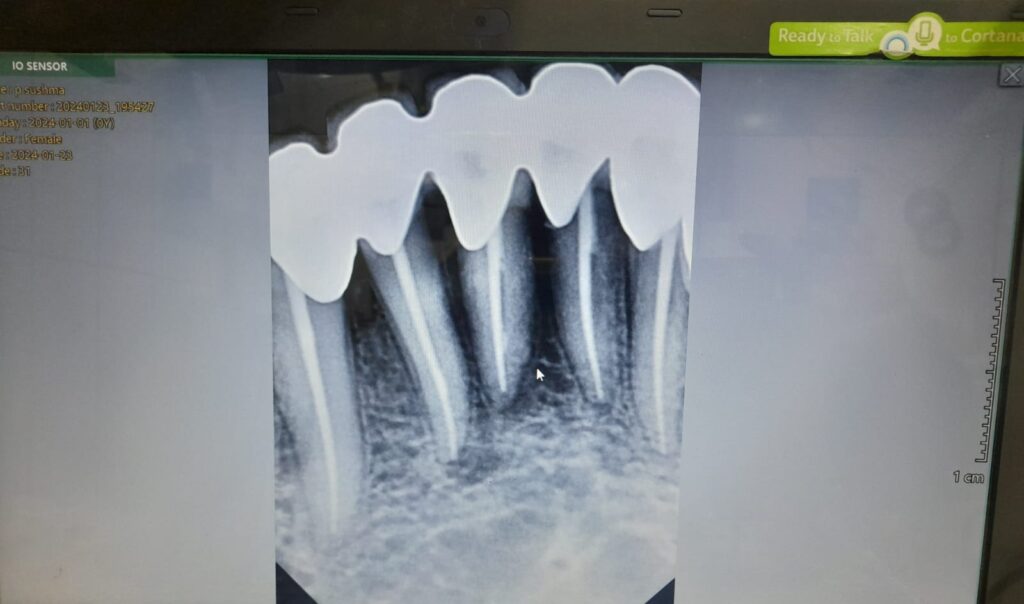

During the procedure, a dentist carefully removes the infected or damaged pulp from the tooth’s root canals, where nerves and blood vessels reside. This infected tissue often causes pain, swelling, and, if untreated, can lead to abscess formation or tooth loss. The Center uses advanced technology to thoroughly clean, disinfect, and shape the root canals to eliminate any remaining bacteria or debris.

The canals are then filled with a biocompatible material and sealed to prevent further infection. Afterward, a dental crown or filling is typically placed to restore the tooth’s structure and function, allowing the tooth to function normally without the risk of reinfection. Choosing the Best Root Canal Treatment Centerensures long-lasting results and a pain-free dental experience.